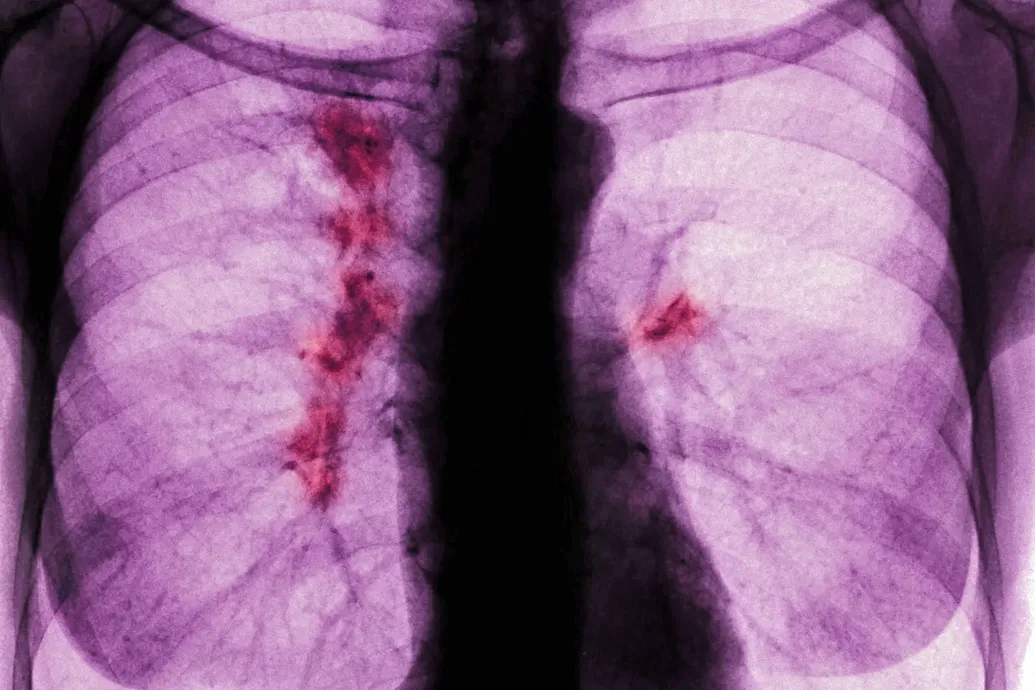

Bár a statisztikák szerint javul a halálozási tendencia, egyre több soha nem dohányzó fiatalt is érint a betegség. Ha időben felismerik, az életet menthet.

A tüdőrák egy aljas, sunyi betegség, és nincs rá állami szűrőprogramunk sem